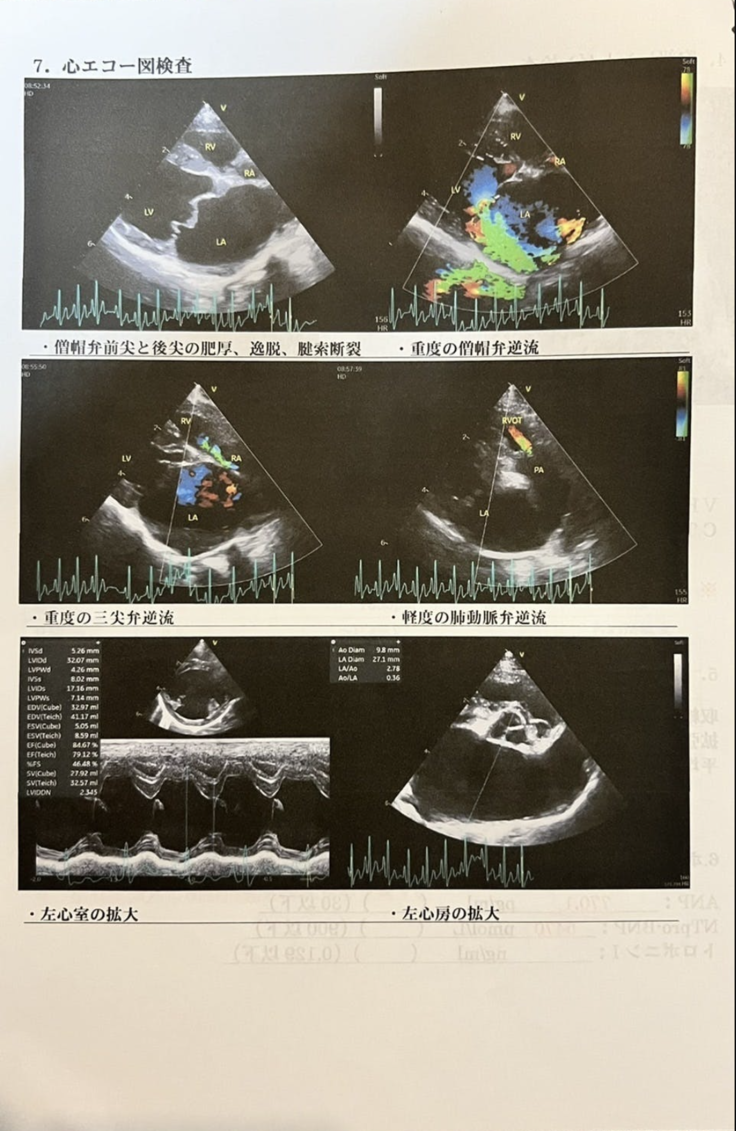

ランが僧帽弁閉鎖不全症(そうぼうべんへいさ ふぜんしょう)と診断されたのは、今年の1月中旬のことです。

僧帽弁閉鎖不全症は心臓病の一種で、左心房から左心室の弁がうまく機能しなかったり、心臓に水が溜まり膨張して他の器官を圧迫してしまったり最後は肺水腫を起こして亡くなってしまう病気です。

ランは肺水腫と診断されました。レントゲンに写る肺はうっすらと白くなっており、心臓の逆流した血液の液体成分が毛細血管から滲み出て肺に漏れてこのように写るのだそうです。

定期検診にはひと月早かったのですが、病院へ連れて行くと心臓が再び肥大化していました。

その肥大した心臓が気管を圧迫したため(気管支軟化症を併発)、苦しそうに何度も咳をしていたようです。